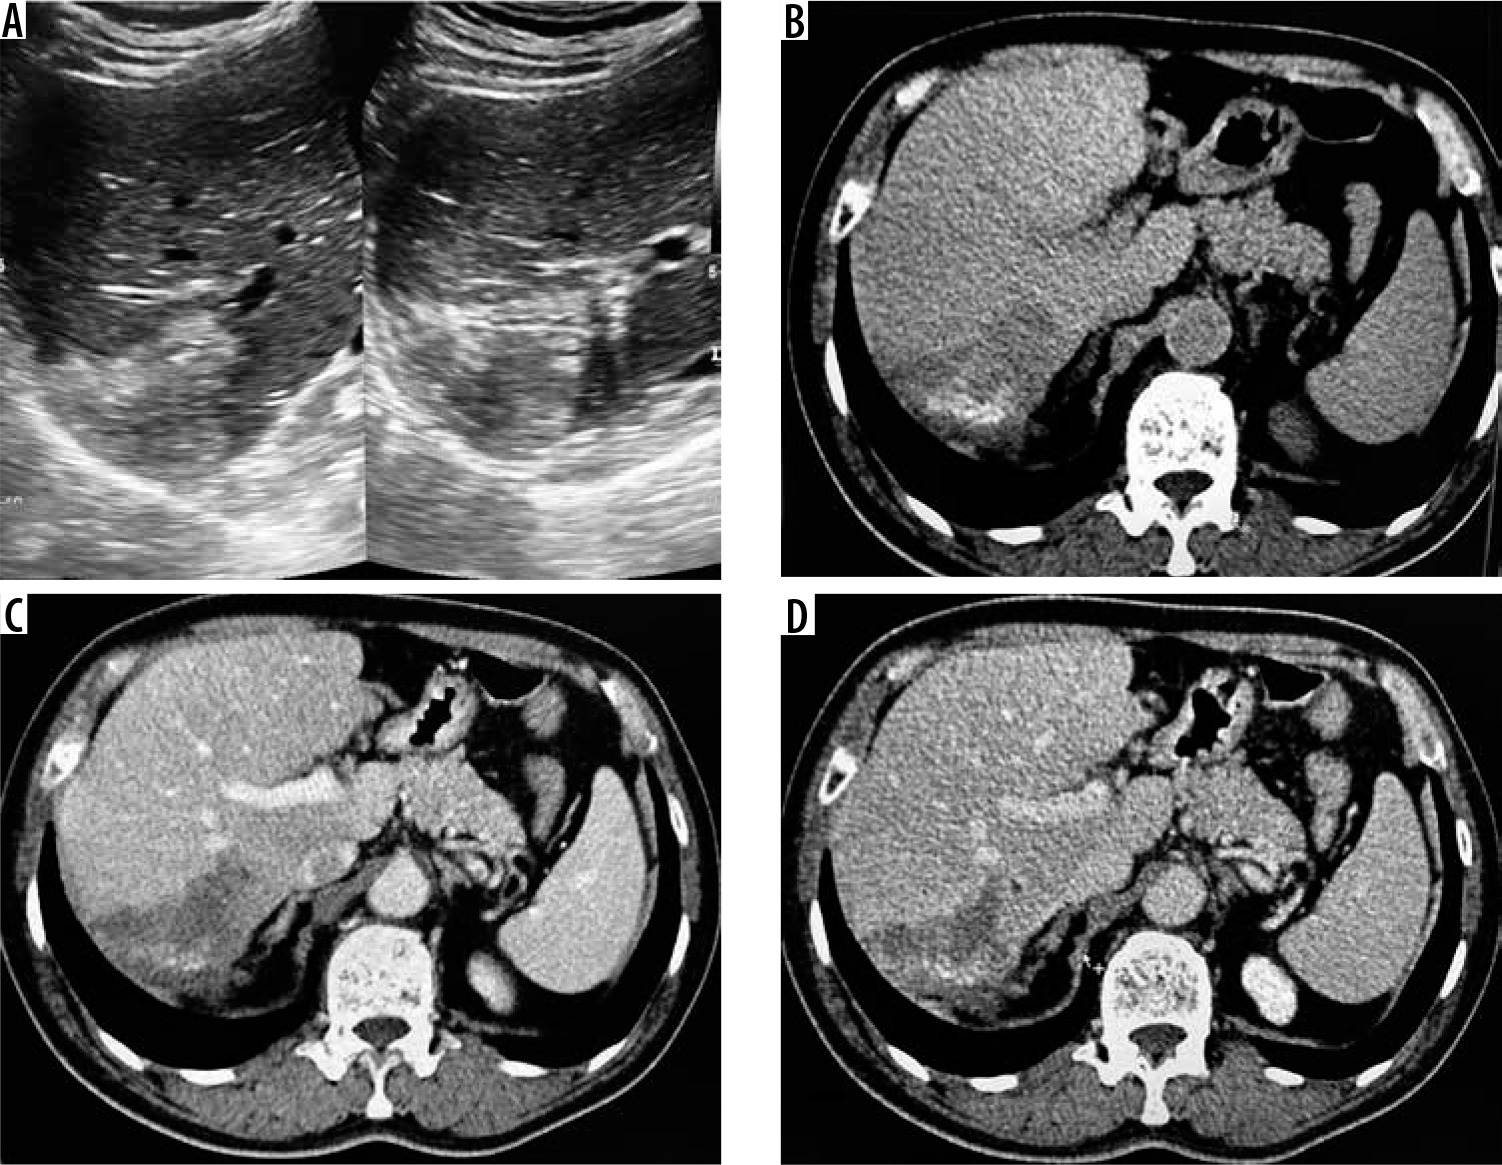

Ultrasonography revealed features of ill-defined, heterogeneously hyper-echoic hepatic mass lesion with no detectable calcification in 12 cases (52%) (Figure 1). Eight patients (34.7%) showed ill-defined hyperechoic hepatic mass with scattered foci of calcification (Figure 2). Two patients showed complex hepatic mass with heterogeneous solid component and associated cystic areas. And one patient showed thick-walled cystic lesion with calcifications in the wall.

Figure 1

A) Transverse ultrasound image of liver shows a peripheral wedge-shaped hyperechoic mass in segment VII. B) Non-contrast axial computed tomography (CT) image shows wedge-shaped hypodense mass with central calcifications. Post-contrast axial CT image in portal phase (C) and hepatic venous phase (D) does not reveal any enhancement of the lesion. No biliary dilatation or vascular invasion is seen (P1 disease)

Figure 2

A) Transverse sonogram of liver shows a large heterogeneously hyperechoic mass with central foci of calcification (arrow). B) Axial non-contrast computed tomography (CT) image shows hypodense mass with central calcification (arrow). Post-contrast axial CT images (C, D) do not reveal any enhancement of the mass. There is left lobe biliary dilatation (P2 disease)